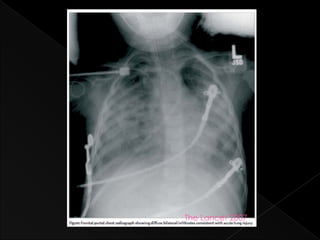

› ALI

 Acute pulmonary failure with PaO2/FiO2 <300mmHg

 Bilateral infiltrates on chest film

 PCWP <18 mmHg, or no clinical evidence of elevated LAP

The Lancet 2007

Acute inflammatory lung injury › resulting from direct or indirect pulmonary insult  American-European Consensus Conference (1994) definitions: › ALI  Acute pulmonary failure with PaO2/FiO2 <300mmHg  Bilateral infiltrates on chest film  PCWP <18 mmHg, or no clinical evidence of elevated LAP › ARDS  as above, with PaO2/FiO2 <200mmHg, regardless of PEEP